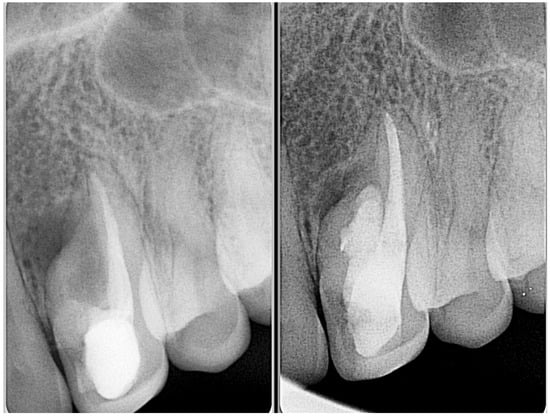

| Type I | Minimal risk to pulp unless caries or bacterial ingress occurs | Periapical radiograph may be adequate | Preventive sealing of palatal pit or groove with resin-based materials Restoration if necessary Endodontic treatment only if secondary infection occurs | Good prognosis and early intervention help preserve pulp vitality Regular clinical and radiographic monitoring |